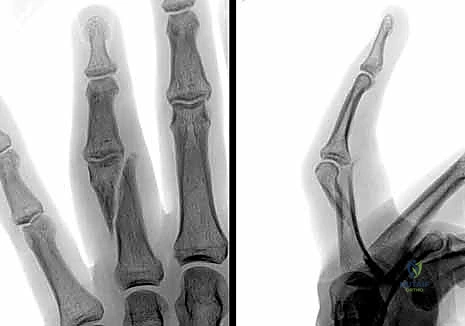

- التصوير بالأشعة السينية (X-rays): هو المعيار الذهبي لتشخيص كسور السلاميات. يطلب الدكتور هطيف دائماً ثلاث وضعيات أساسية:

- الأمامية الخلفية (AP View).

- الجانبية الحقيقية (True Lateral View): وهي الأهم لتقييم مقدار الانزياح الزاوي.

- المائلة (Oblique View): تساعد في رؤية الكسور الشعرية الدقيقة أو الكسور المفصلية الخفية.

تُعد هذه الطريقة الأقل توغلاً. يقوم الدكتور هطيف برد الكسر يدوياً تحت توجيه جهاز الأشعة السينية المباشر (C-arm) في غرفة العمليات، ثم يقوم بإدخال أسلاك معدنية دقيقة (K-wires) عبر الجلد لتثبيت العظم.